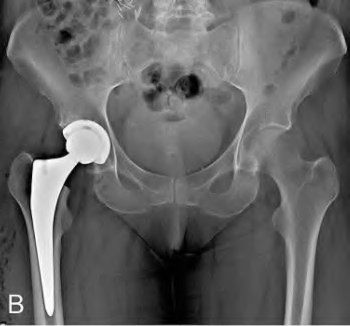

A 72-year-old female falls and sustains a periprosthetic femur fracture around her cementless total hip arthroplasty. Radiographs reveal a fracture extending just distal to the tip of the stem. The stem is radiographically loose, but there is excellent proximal and distal bone stock. According to the Vancouver classification, what is the fracture type and the recommended surgical treatment?

Explanation

Question 23

A 75-year-old female sustains a fall 5 years after a cementless THA. Radiographs show a periprosthetic femur fracture occurring around the stem tip. Intraoperative assessment reveals the stem remains firmly fixed in the metaphysis, and the proximal bone stock is adequate. According to the Vancouver classification, what is the fracture type and the standard recommended treatment?